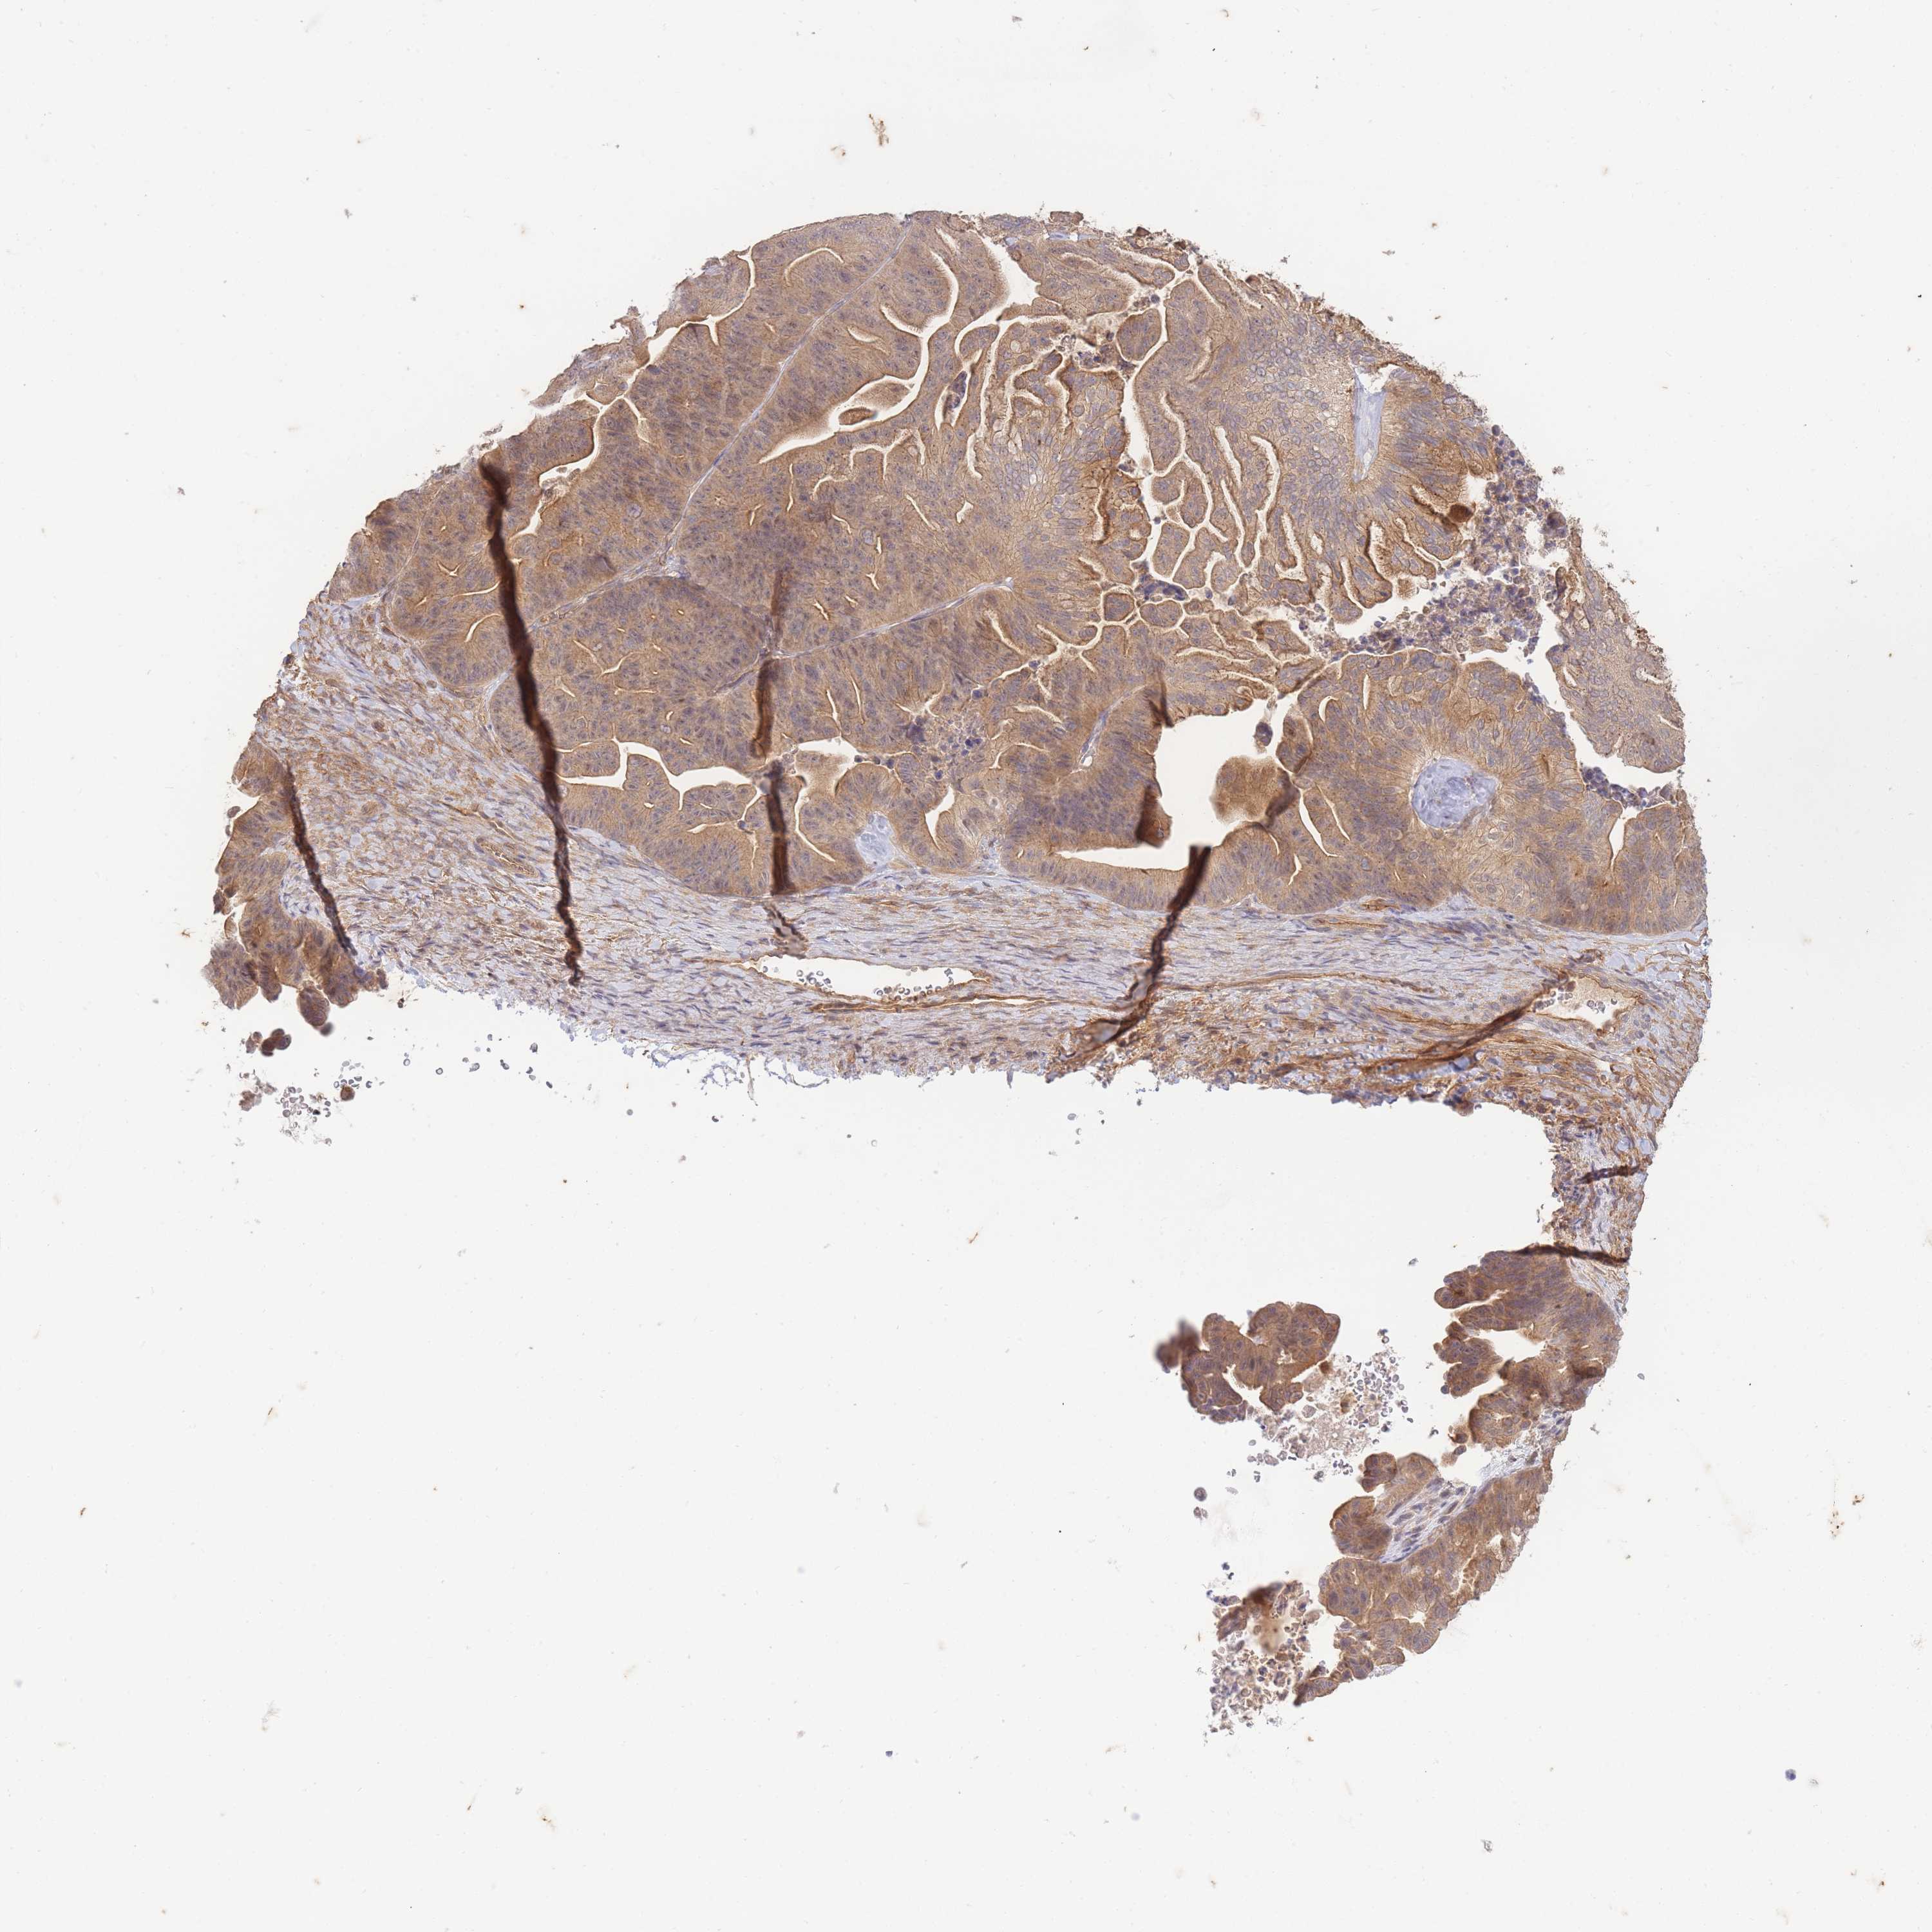

OVARIAN CANCER - Protein expressioni

A mouse-over function shows sample information and annotation data. Click on an image to view it in a full screen mode. Samples can be filtered based on level of antibody staining by selecting one or several of the following categories: high, medium, low and not detected. The assay and annotation is described here.

Note that samples used for immunohistochemistry by the Human Protein Atlas do not correspond to samples in the TCGA dataset.

Antibody stainingi

Antibody staining in the annotated cell types in the current human tissue is reported as not detected, low, medium, or high, based on conventional immunohistochemistry profiling in selected tissues. This score is based on the combination of the staining intensity and fraction of stained cells.

Each image is clickable and will lead to virtual microscopy that enables deeper exploration of all samples and also displays staining intensity scores, fraction scores and subcellular localization as well as patient and tissue information for each sample.

Antibody HPA051126

Staining

High

Medium

Low

Not detected

Intensity

Strong

Moderate

Weak

Negative

Quantity

>75%

75%-25%

<25%

None

Location

Nuclear

Cytoplasmic/membranous

Cytoplasmic/membranous,nuclear

Cystadenocarcinoma, serous, NOS

Carcinoma, NOS

Cystadenocarcinoma, mucinous, NOS

Carcinoma, endometroid